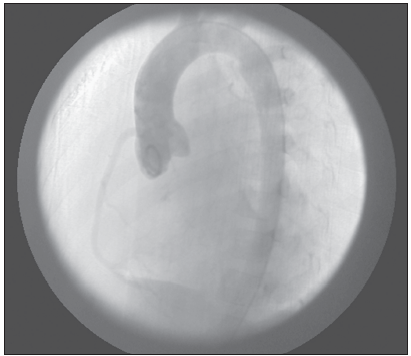

Cardiac catheterization revealed a single anterior coronary artery (the right coronary artery) arising from the aorta and an aberrant left coronary artery arising from the pulmonary artery (Figure 2).